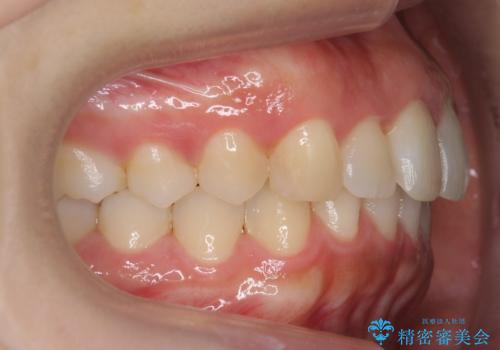

出っ歯の治療 抜かずに 短期間で目立たない治療

- 前歯のがたつきと突出を主訴に来院。

歯を抜かずに非抜歯で治療しました。

治療にも大変満足していただきました。

リファインメントも1回で済んでいます。